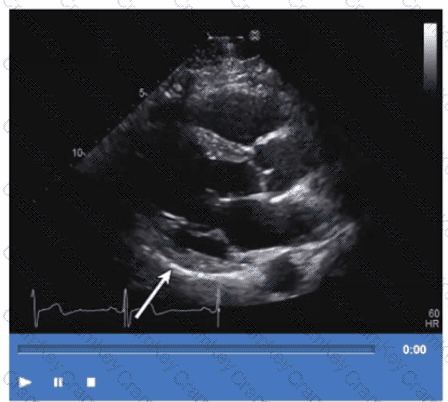

Which wall is indicated by the arrow on this video?

Options:

A.

Anteroseptum

B.

Anterolateral

C.

Inferoseptum

D.

Inferolateral